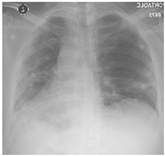

Furthermore, some of the examples of the COVID-19 positive and the healthy patients from the dataset are included in Table 5. The clinical data represent the attributes sequence, i.e., gender, age, body temperature, pulse rate, respiratory rate, blood pressure systolic, blood pressure diastolic, shortness of breath, cough, other symptoms, diabetes mellitus, hypertension, cardiac disease, dyslipoproteinemia, chronic kidney disease, and other chronic diseases.

COVID-19 Positive Sensors 22 00669 i001Male, 68, 37, 70, 27, 129, 76, Y, Y, asymptomatic, Y, Y, Y, Y, N, anemia